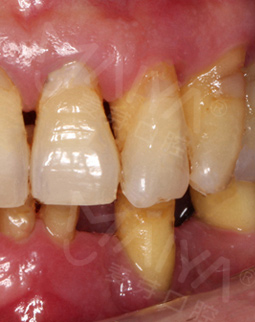

麦芽的博士专家团在看过我的片子后发现,我的牙齿由于长期对口腔疏于护理,牙周情况非常差,余牙有些松动,且牙槽骨萎缩严重,现存的骨量无法进行传统的种植牙手术,因此给我设计了“all-on-4”种牙技术的升级版本“all-on-5”,前期是要处理我的牙周问题,当天就给安排了洁牙,然后上药,等牙周恢复差不多就可以进行种植了!

经过一个月的牙周治疗,牙齿肿胀部分都已经消退,来麦芽种牙之前,心理还有点小紧张,总害怕种牙特别疼,恢复时间慢。我的牙齿情况比较复杂,部分牙齿有牙槽骨吸收,经过前期的各种检查,医生说我的身体状况适合种牙。